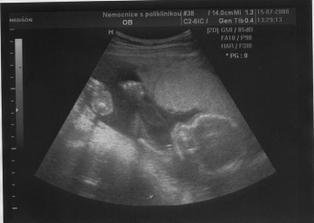

Ve 30.tt jsem šla na další utz,Honzík už má 1600g a je otočený hlavičkou dolů 🙂

Ve 35.tt mě můj doktor posílá už na starost do nemocnice,kvůli tomu tvrdnutí,ten den jsem strávila v nemocnici 7hodin,to bylo opravdu náročné - 2h u mého doktora,2h na utz,1h na natáčkách a 2h na ambulanci.. UTZ ve 35.tt - Honzík má 2590g,

,už je krásně natlačený dolů,že mu ani nešlo změřit hlavičku,opět mi Dr. říká,že porodím dříve..Mám CS 5